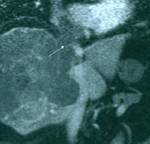

Results: Twenty-two cardiac masses were successfully detected and their characteristics adequately delineated, including eight myxomas, one angiosarcoma, one ventricular lymphoma, one endocardiac metastasis, one epicardiac paraganglioma, and 10 cases of intracardiac thrombi.